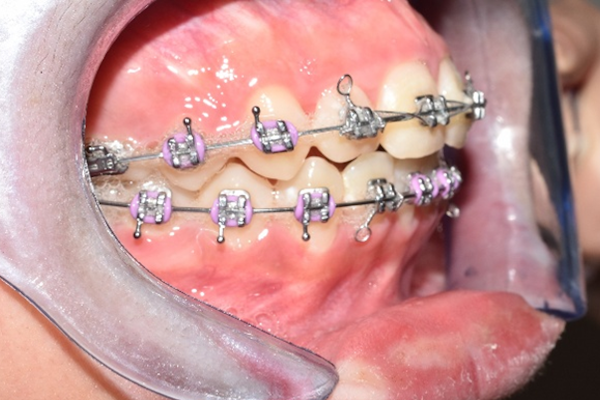

Se colocó ortodoncia fija con brackets metálicos, iniciando la fase de alineación y nivelación. El tratamiento incluye arco ortodóncico para corrección progresiva, ligadura metálica para control de movimientos dentales, y ajustes periódicos para guiar la posición dental.

La paciente en fase inicial de tratamiento

La paciente, muy contenta con el resultado final

La ortodoncia no solo mejora la apariencia, también:

- Corrige la mordida, mejorando la masticación

- Previene desgaste irregular

- Mejora la salud periodontal y reduce el riesgo de caries

- Aumenta la confianza al sonreír